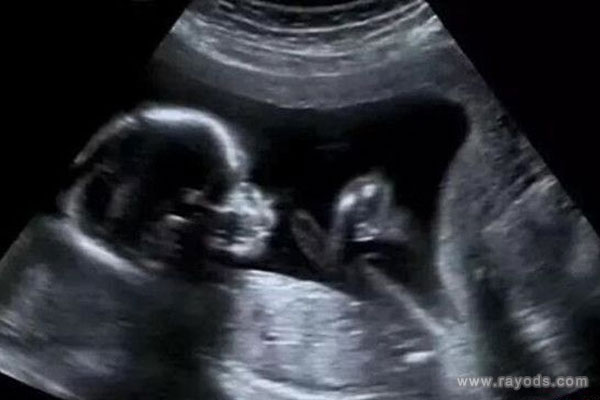

胎儿b超数据标准对照表,教你一秒看懂B超单(推荐收藏)!很多人都说,生宝宝是一场修行,但是对于不少非医学的准妈妈来说,这何止是种修行,简直是修学分啊!每一次B超都是一场随堂考,BDP是啥?HC是啥?FL是啥?羊水指数、胎盘位置、胎方位又是啥?所以说,今天我带大家一起来解读B超单,目的不是为了让大家自学成材,而是让大家在看到B超报告单时,能做到心中有数。